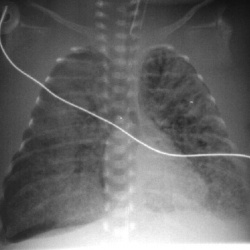

По поводу Пневмоторакса. У новорожденных бывают складки кожи (Skin Folds), тень от которых, можно принять за пневмоторакс (см).